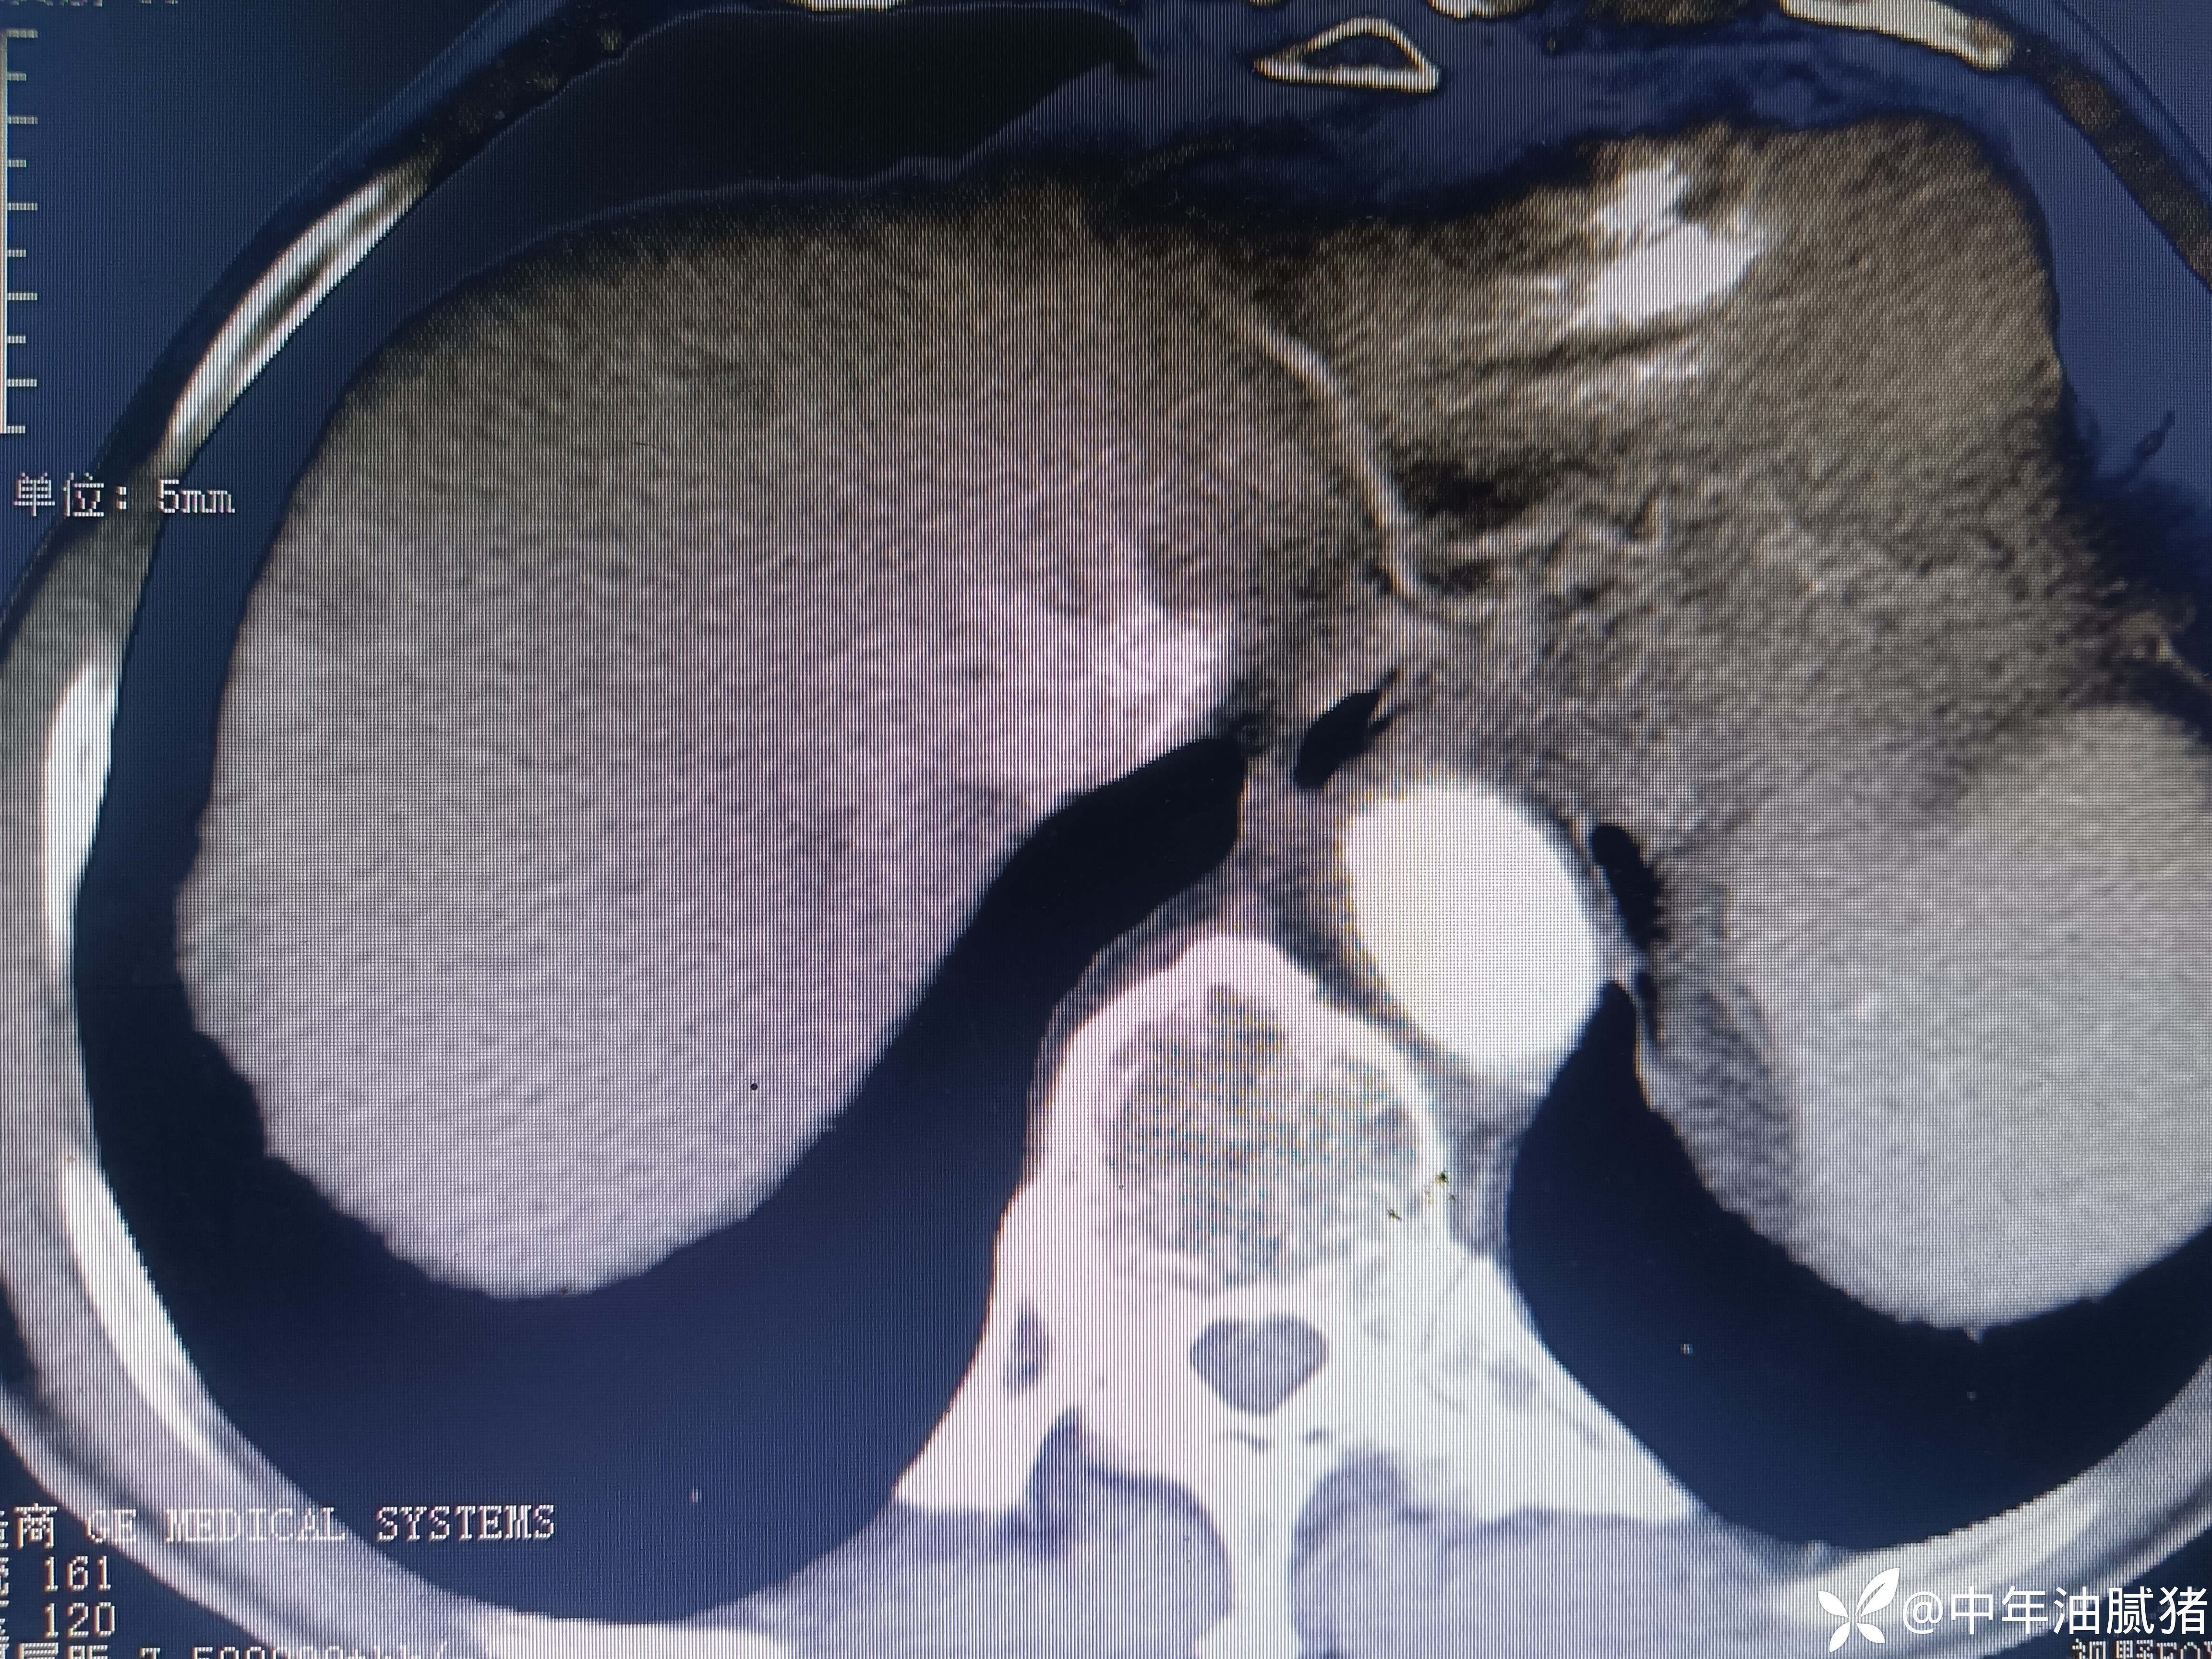

肺ct看到肝内病灶,行增强检查

男,72岁,感胸痛7天,不剧,咳嗽时略明显,有吸烟,行肺ct报告如下

建议增强ct.报告如下

考虑肝囊肿?让他走?

看后,我隐隐约约觉的不是肝囊肿那么简单?元芳,你怎么看?狄阁老,我也是这么认为!摇人,掏起手机:喂,w主任,请帮我看看这个ct。5分钟后报告修改如下